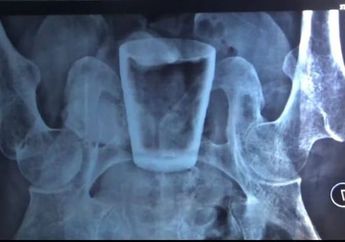

Gelas Kaca Bersarang di Perut Pria Asal Jember hingga Bikin Dokter Geleng Kepala, Mbah Mijan Turun Gunung Singgung Soal Santet Salah Sasaran!

3 Tahun yang lalu - Inilah sosok Nur Lasidi, pria asal Jember yang terdapat gelas kaca utuh di dalam perutnya, Mbah Mijan singgung soal santet.

Aneh Tapi Nyata, Gelas Kaca Ditemukan di Dalam Perut Seorang Pria di Jember, Berawal dari Merasakan Sakit di Ulu Hati

3 Tahun yang lalu - Sungguh aneh, pria asal Jember, Jawa Timur ini alami sakit di bagian ulu hati, saat di-rontgent, ternyata dalam tubuhnya terdapat gelas kaca.